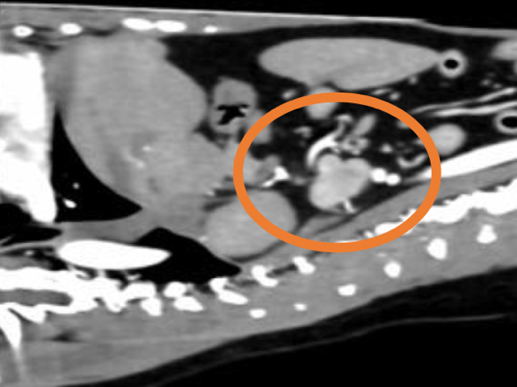

後大静脈に浸潤している副腎腫瘍(緑丸)

副腎腫瘍の中には、後大静脈などの重要な血管の中に腫瘍が入り込む(血管内浸潤)タイプがあります。このような場合、手術はさらに高度で慎重な対応が求められます。 当院では、術前にCT検査などを用いて正確な病態を把握し、安全に手術を実施する体制を整えております。必要に応じて、外科専門医や麻酔専門医がチームで対応いたします。

2. 術当日全身麻酔下で腫瘍を摘出します。血管内に腫瘍がある場合には、血管を開いて腫瘍を取り除く処置が必要になることもあります。